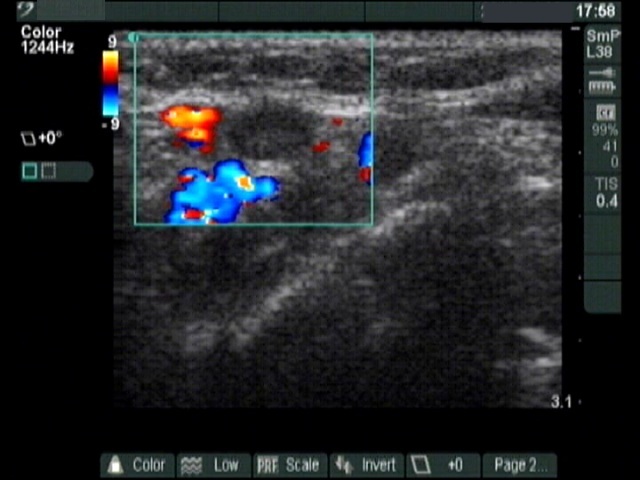

Thyroid cancers - case 185 (ultrasonographic picture 10)

Above the left lobe, transverse scan, color Doppler mode. There is an enlarged lymph node surrounded with vessels.